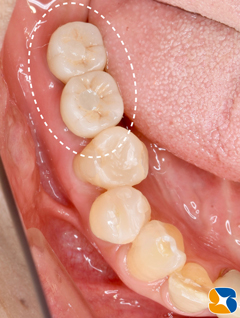

施術より3ヶ月後、インプラント完成。

施術から3ヶ月後、インプラント完成。

適合の良くなかった前歯もセレックを使って、オールセラミックスに順次やり変え。